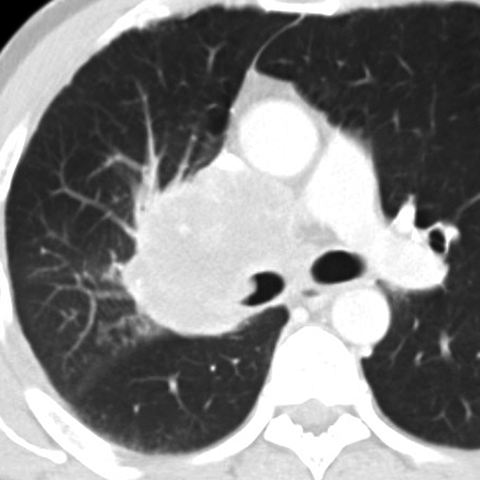

Hilar Nodes in Lung Cancer [3 of 3]